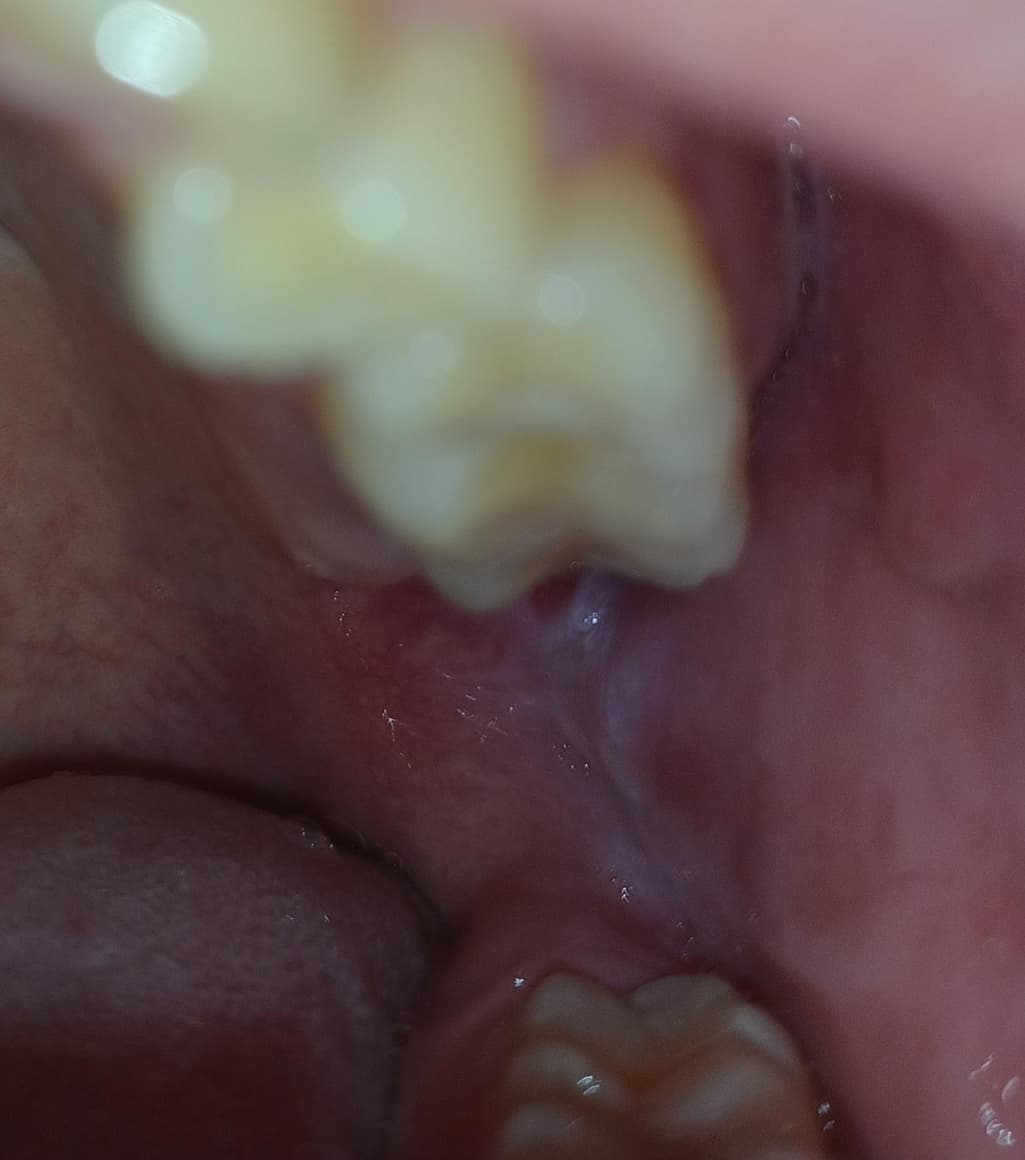

3일째인데 통증이 더 심해져서 확인해보니까 붉은색이 조금 보이던데 구내염일까요?

작년에는 구내염이 생겼을때는 저런식으로 붉은색은 안보였었는데 이것도 그냥 놔두면 1~2주면 괜찮아지겠죠?

구내염인가요? 아니면 다른걸까요? -> 사진상으론 구내염 양상 같습니다. 자극적인 음식 피하시고 1~2주 정도 증상 지켜보시죠1명 평가안녕하세요. 안상우 치과의사입니다.

사진으로는 정확한 확인이 어려워 보입니다. 구내염은 몸의 면역력이 떨어진 상태에서 점막 조직에 손상이 가해 지게 되고 감염이 되어 생기게 됩니다. 결과적으로 몸의 면역력이 떨어지지 않도록 충분한 휴식을 취해주는 것이 좋습니다.

사진이 명확하진 않지만 단순 구내염일 가능성이 높아보입니다. 며칠 지나면 사라질겁니다.

사진에 보이는건 볼살이 치아에 씹혀서 생긴 상처 같은겁니다. 사랑니 때문에 그럴수도 잇으니 치과에 가셔서 검진을 받아보세요.